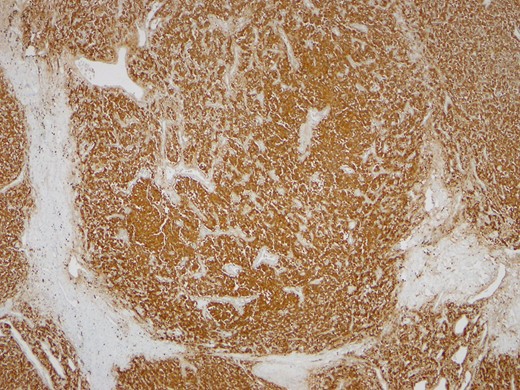

One month later the patient was reoperated via an open approach, which revealed a tumoral lesion in the inter-aorto-cava location, from the right diaphragmatic pillar to the right renal artery. No intraoperative complications were reported and the post-operative period was uneventful. Histological result revealed an 84 g capsulated, solid tumor, with 80 × 60 × 25 mm3. Immunohistochemistry revealed positivity for chromogranin and synaptofisin, compatible with paraganglioma (Figs 4–6). No vascular, lymphatic or capsular invasion was ocumented.